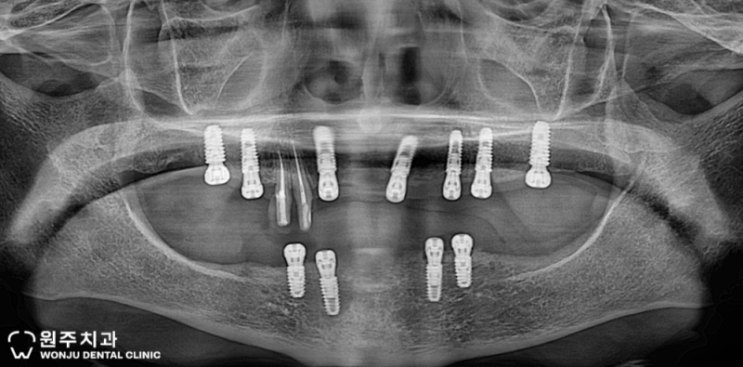

원주임플란트 원주치과 구강악안면외과전문의 김영욱원장님 - 포스팅공유 :) / 성남시 치과의사회 회의실 7월 17일 하이니스 임플란트 보철 세미나 추천

안녕하세요 :) 원주치과의원입니다. 팀장님께서 최근에 올리신 포스팅 공유드립니다. 틀니를 사용하시는 환...